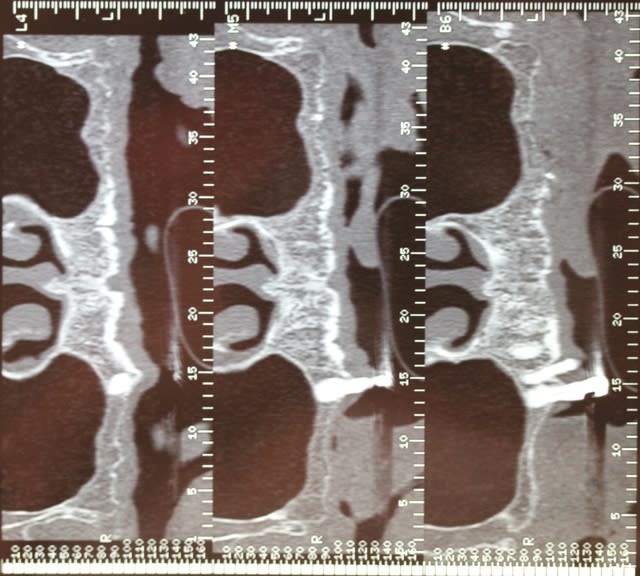

Le dentascan de la mandibule pour que vous compreniez mieux la difficulté...quais impossible de la considérer en cylindres même en déplaçant le NDI vous n avez aucune hauteur exploitable... Même des lame de Likow n y passent pas et les sous périostés sont interdits en Europe

J ai perdu mes deux foutus cylindres et ai dû les remplacer par deux double disk...et changer les deux mono disk du secteur droit

Et oui l implanto basale n est pas non plus un long fleuve tranquille